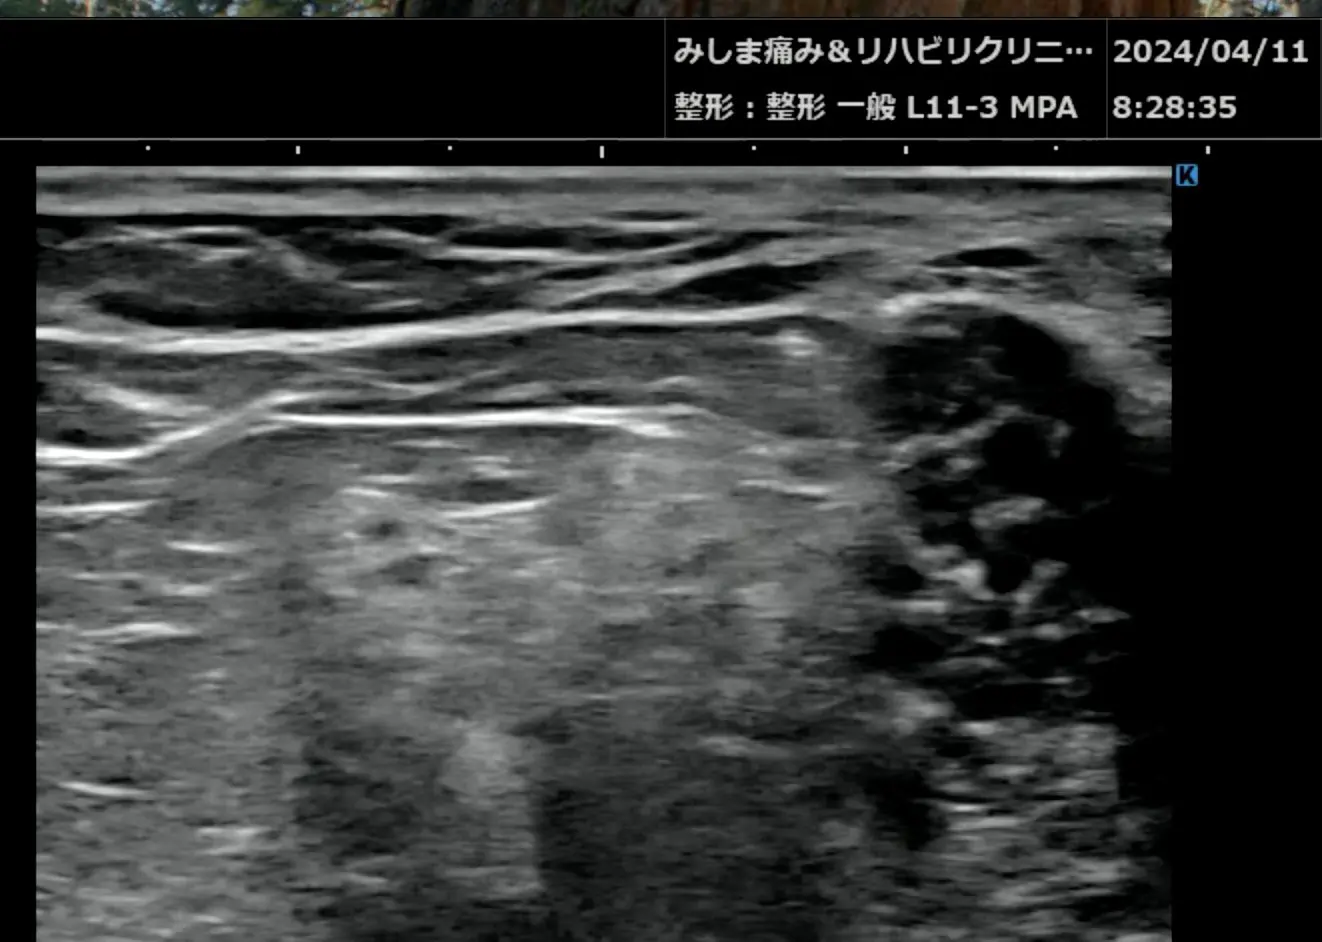

基本的には私は超音波装置を使うのが好きです。超音波は簡便に筋肉や靭帯、そしてターゲットとなる神経を出すことができます。

体の神経の至るところ全て出すことができるので、ほとんど超音波をマスターすればことが足りるのです。

超音波(エコー)

こちらは坐骨神経